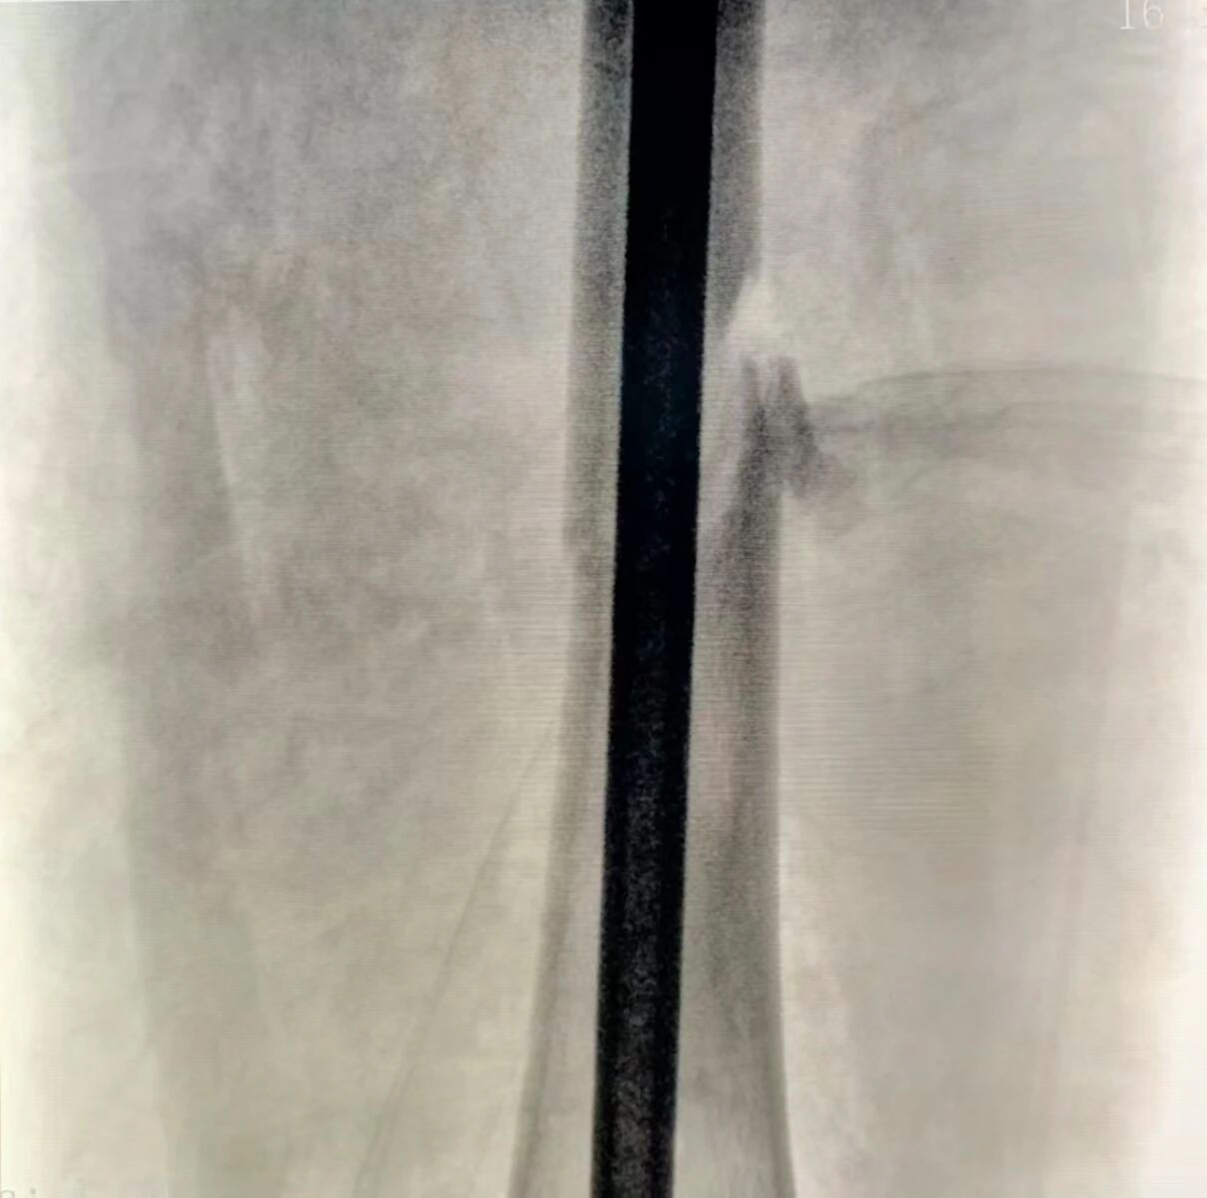

面对这一复杂情况,骨三科团队迅速制定了个性化微创方案,成功实施 “闭合复位髓内钉内固定术” 。术中,团队凭借丰富的临床经验和娴熟的微创技术,在影像精准引导下,巧妙避开肿瘤影响,顺利置入髓内钉,一举攻克了骨折牢固固定与肿瘤占位并存的难题。该术式仅通过微小切口完成,最大限度保留了骨折端的血液供应,为骨骼愈合创造了优越的生物学环境。

术后